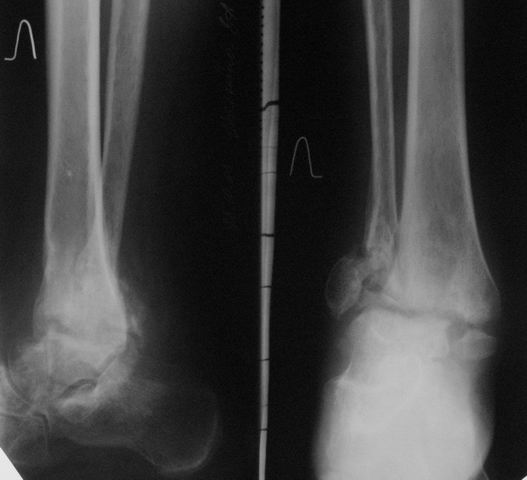

Уважаемые коллеги! Обратилась женщина 45 лет. Травма 2 года назад (март 2005 г.) - открытый 2-х лодыжечный перелом левой голени.

К сожалению, рентгенархив недоступен. Лечилась на вытяжении, затем гипсовой повязкой. Рана у внутренней лодыжки зажила вторичным натяжением. Сращения не наступило. В июне 2005 г. выполнялся артродез по Кэмпбеллу, фиксация в гипсовой повязке 3.5 мес. Сейчас нога полностью неопороспособна, выраженная патологическая подвижность. Признаков инфекции нет. Помогите определиться с методом артродеза, фиксации (КДО?), нужно ли вскрывать сустав, костная пластика? Пациентка, намучавшись за 2 года. "готова на любые эксперименты" (ее слова). Спасибо, с уважением, А. Минервин